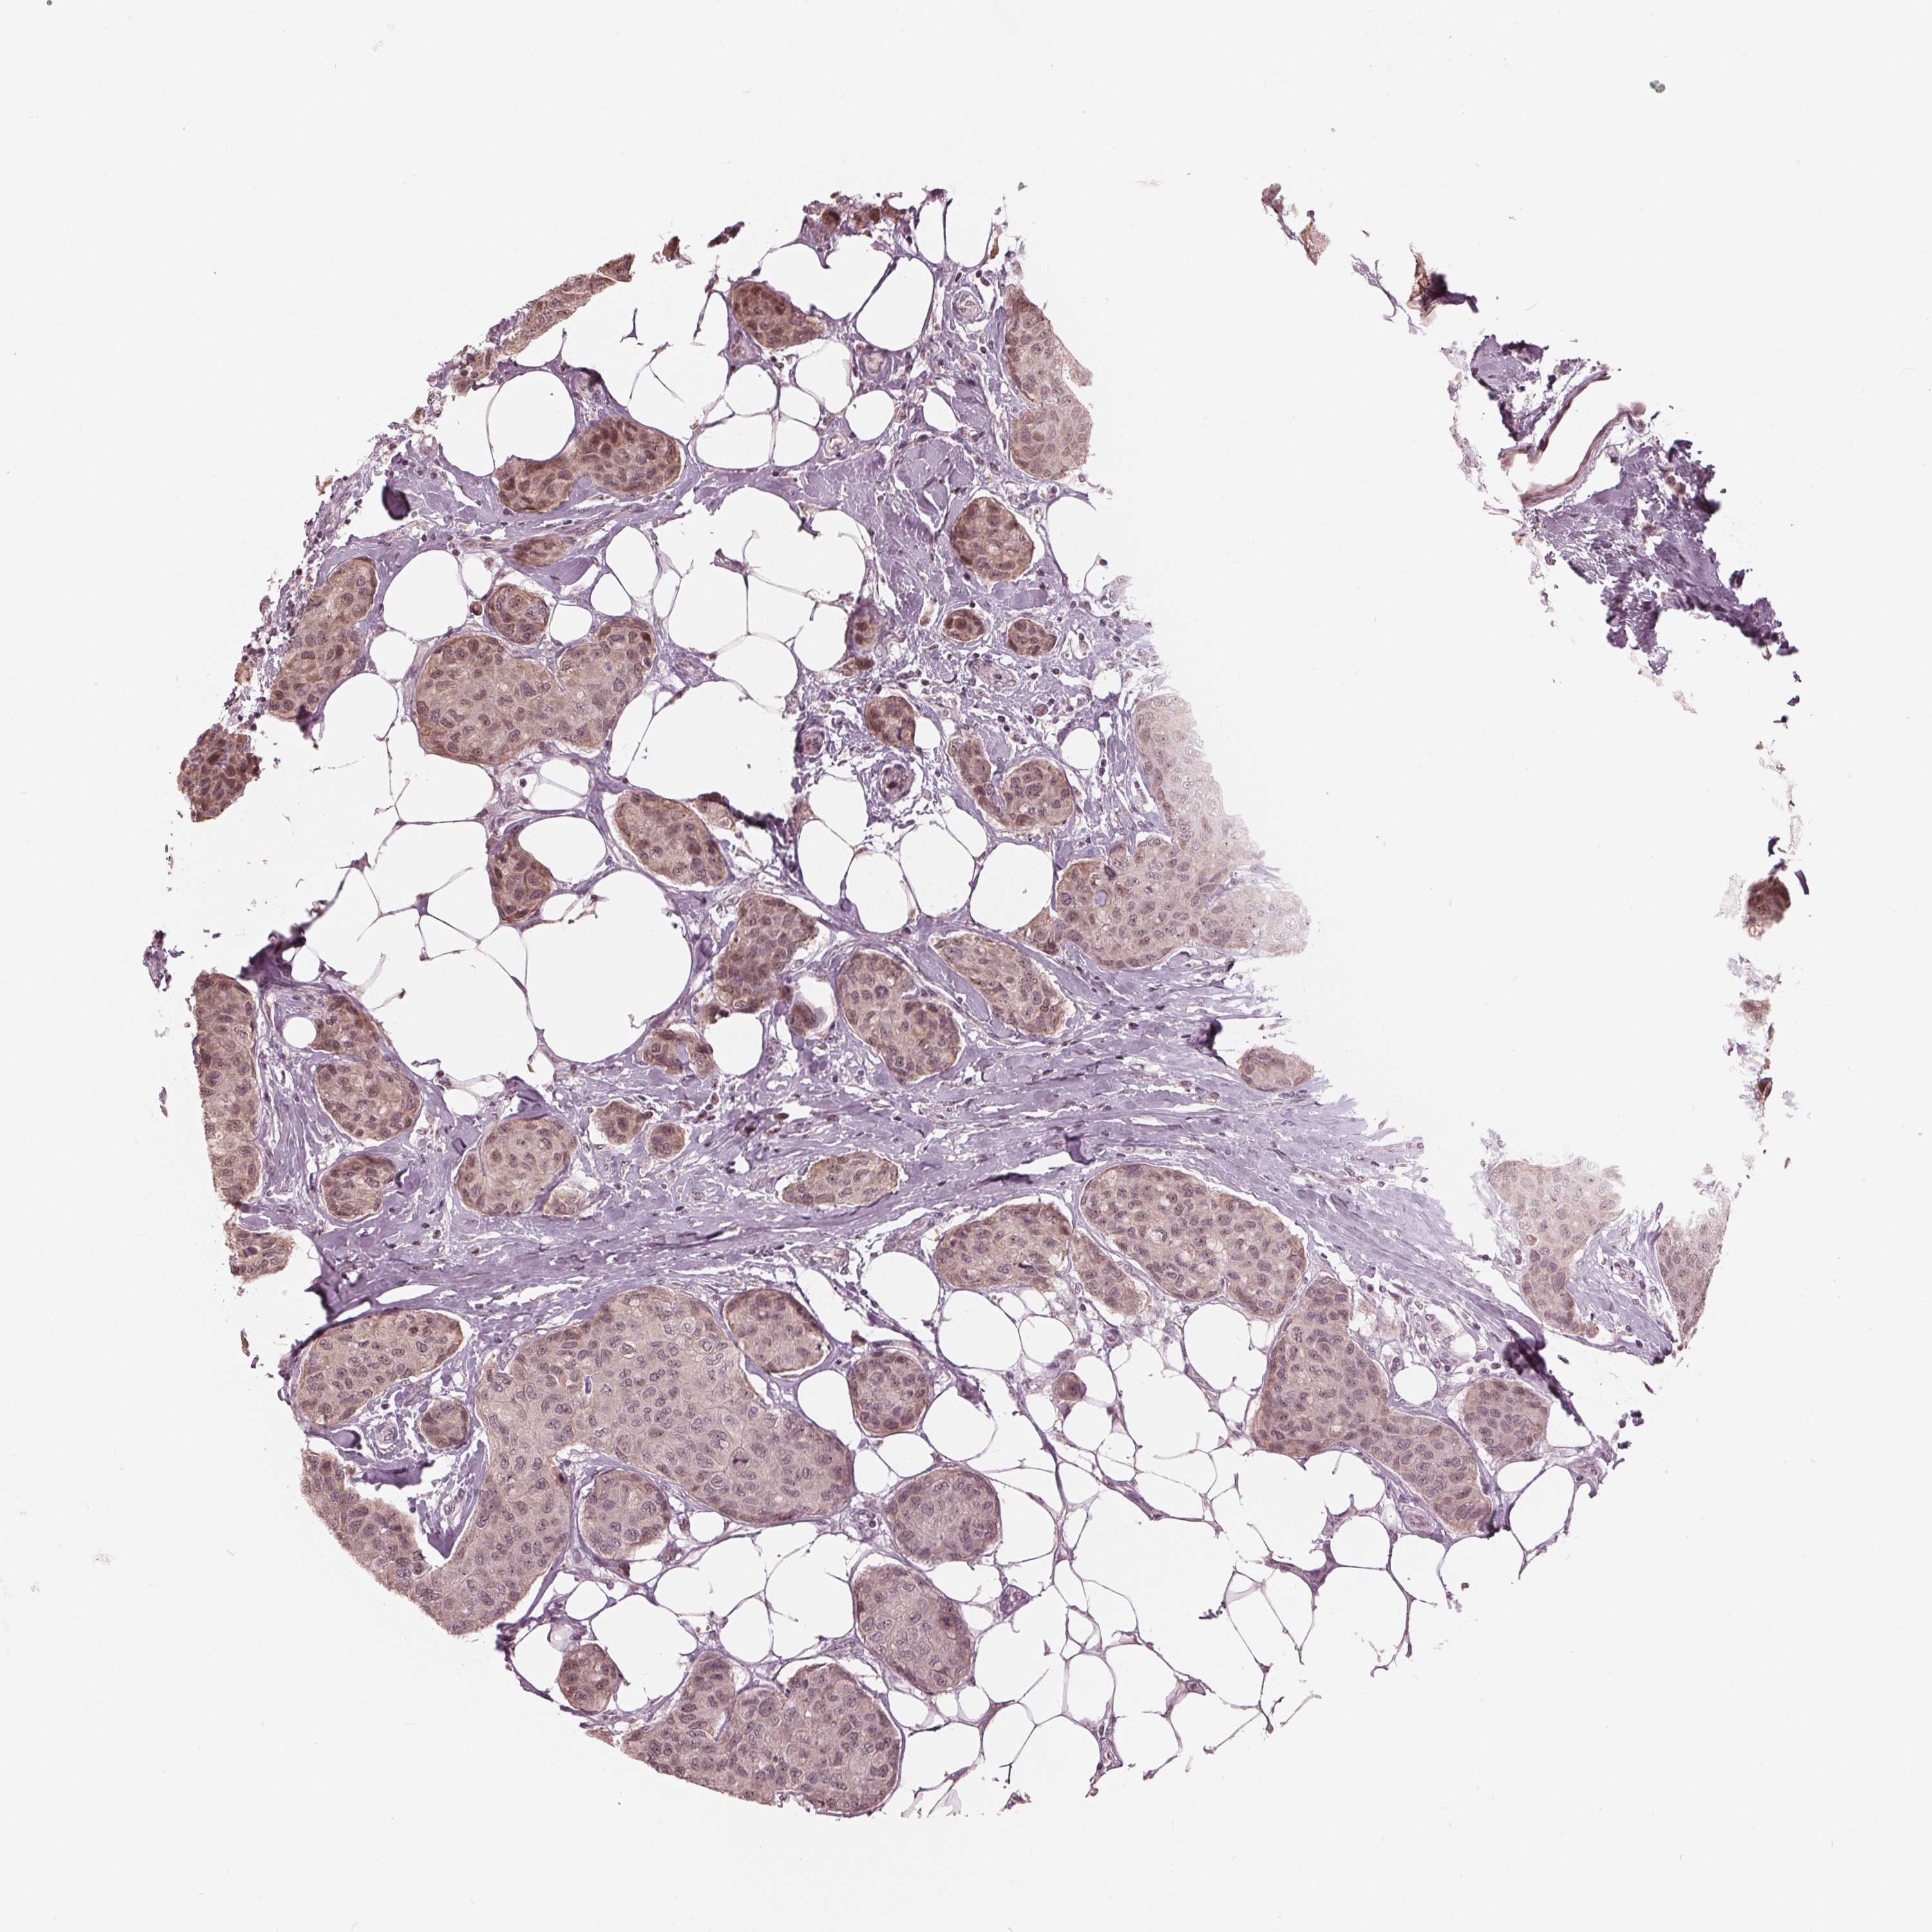

BRCA TCGA BRCA VALIDATION PROTEIN EXPRESSION

Breast cancer

Human cancer